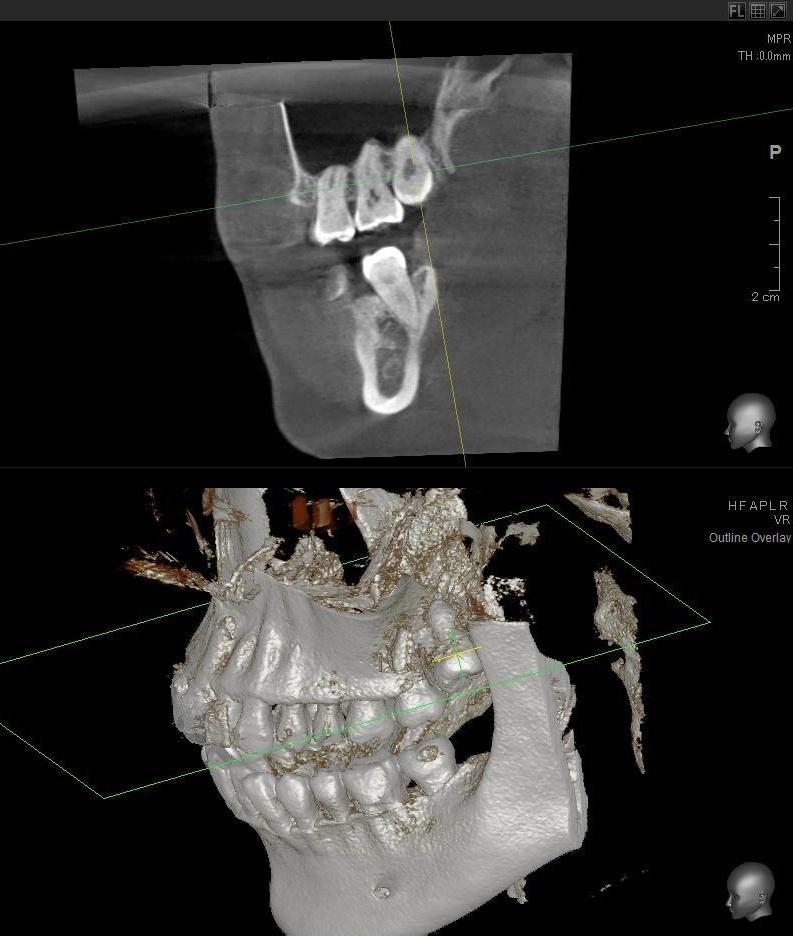

パノラマ写真を撮影してみると、左上の親知らずは歯茎に埋まってはいますが、ほぼまっすぐ生えているのが確認できました。

さらに、上顎の親知らずは上顎洞(副鼻腔)に近接して生えている場合もあるため、CTを撮影して位置関係を詳しく解析します。

上顎の親知らずが上顎洞(副鼻腔)に近い位置に生えている場合や、上顎洞へ突き抜けている可能性がある場合は、大きな病院に紹介する場合もあります。

今回は上顎洞からも距離があるため、抜歯は可能と診断されました。